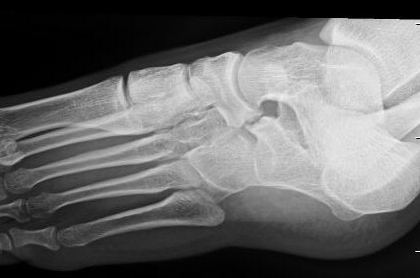

X-ray

Anteater sign

- oblique xray

- elongated process on calcaneum or prolongation of navicular